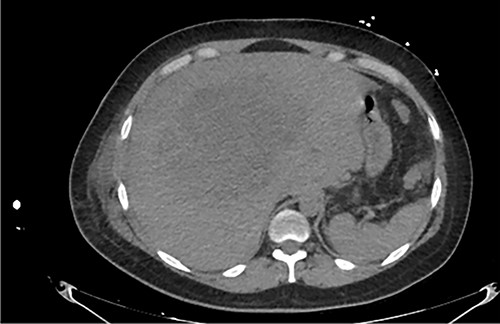

Examination revealed tachycardia, tachypnea, jaundice, dehydration, jugular vein distension, right lung hypoventilation, ascites, upper abdominal tenderness and bilateral lower limb edema. Laboratory workup highlighted neutrophilic leukocytosis, with WBCs exceeding 20 000/μl, along with an abnormal hepatic function panel. The latter showed hypertransaminasemia with ALT predominance over AST (344.7 U/L and 288.5 U/L, respectively), hyperbilirubinemia (10.01 μmol/L) and elevated values of ALP (909.1 U/L) and DHL (709.9 U/L). Of relevance, creatinine elevation (2.11 mg/dl), thrombocytosis (629 × 109/L) and positive D-Dimer (5780 ng/ml) were also noted, so acute kidney injury management and thromboprophylactic measures were initiated. A chest X-ray (CXR) showed a massive right pleural effusion (Fig. 1) and an abdominal ultrasound (US) revealed hepatomegaly with a right nodule (Fig. 2). After further evaluation, tomographic evidence of a right pleural effusion occupying 100% of the lung (Fig. 3) and a 20 cm hypodense, nodular lesion in the right liver (Fig. 4) were identified. These findings were suggestive of an ALA concomitant with an empyema. The patient was admitted into the intensive care unit and prepared for surgery.

Axial abdominal CT at admission: 20 cm nodular lesion occupying the right liver lobe.